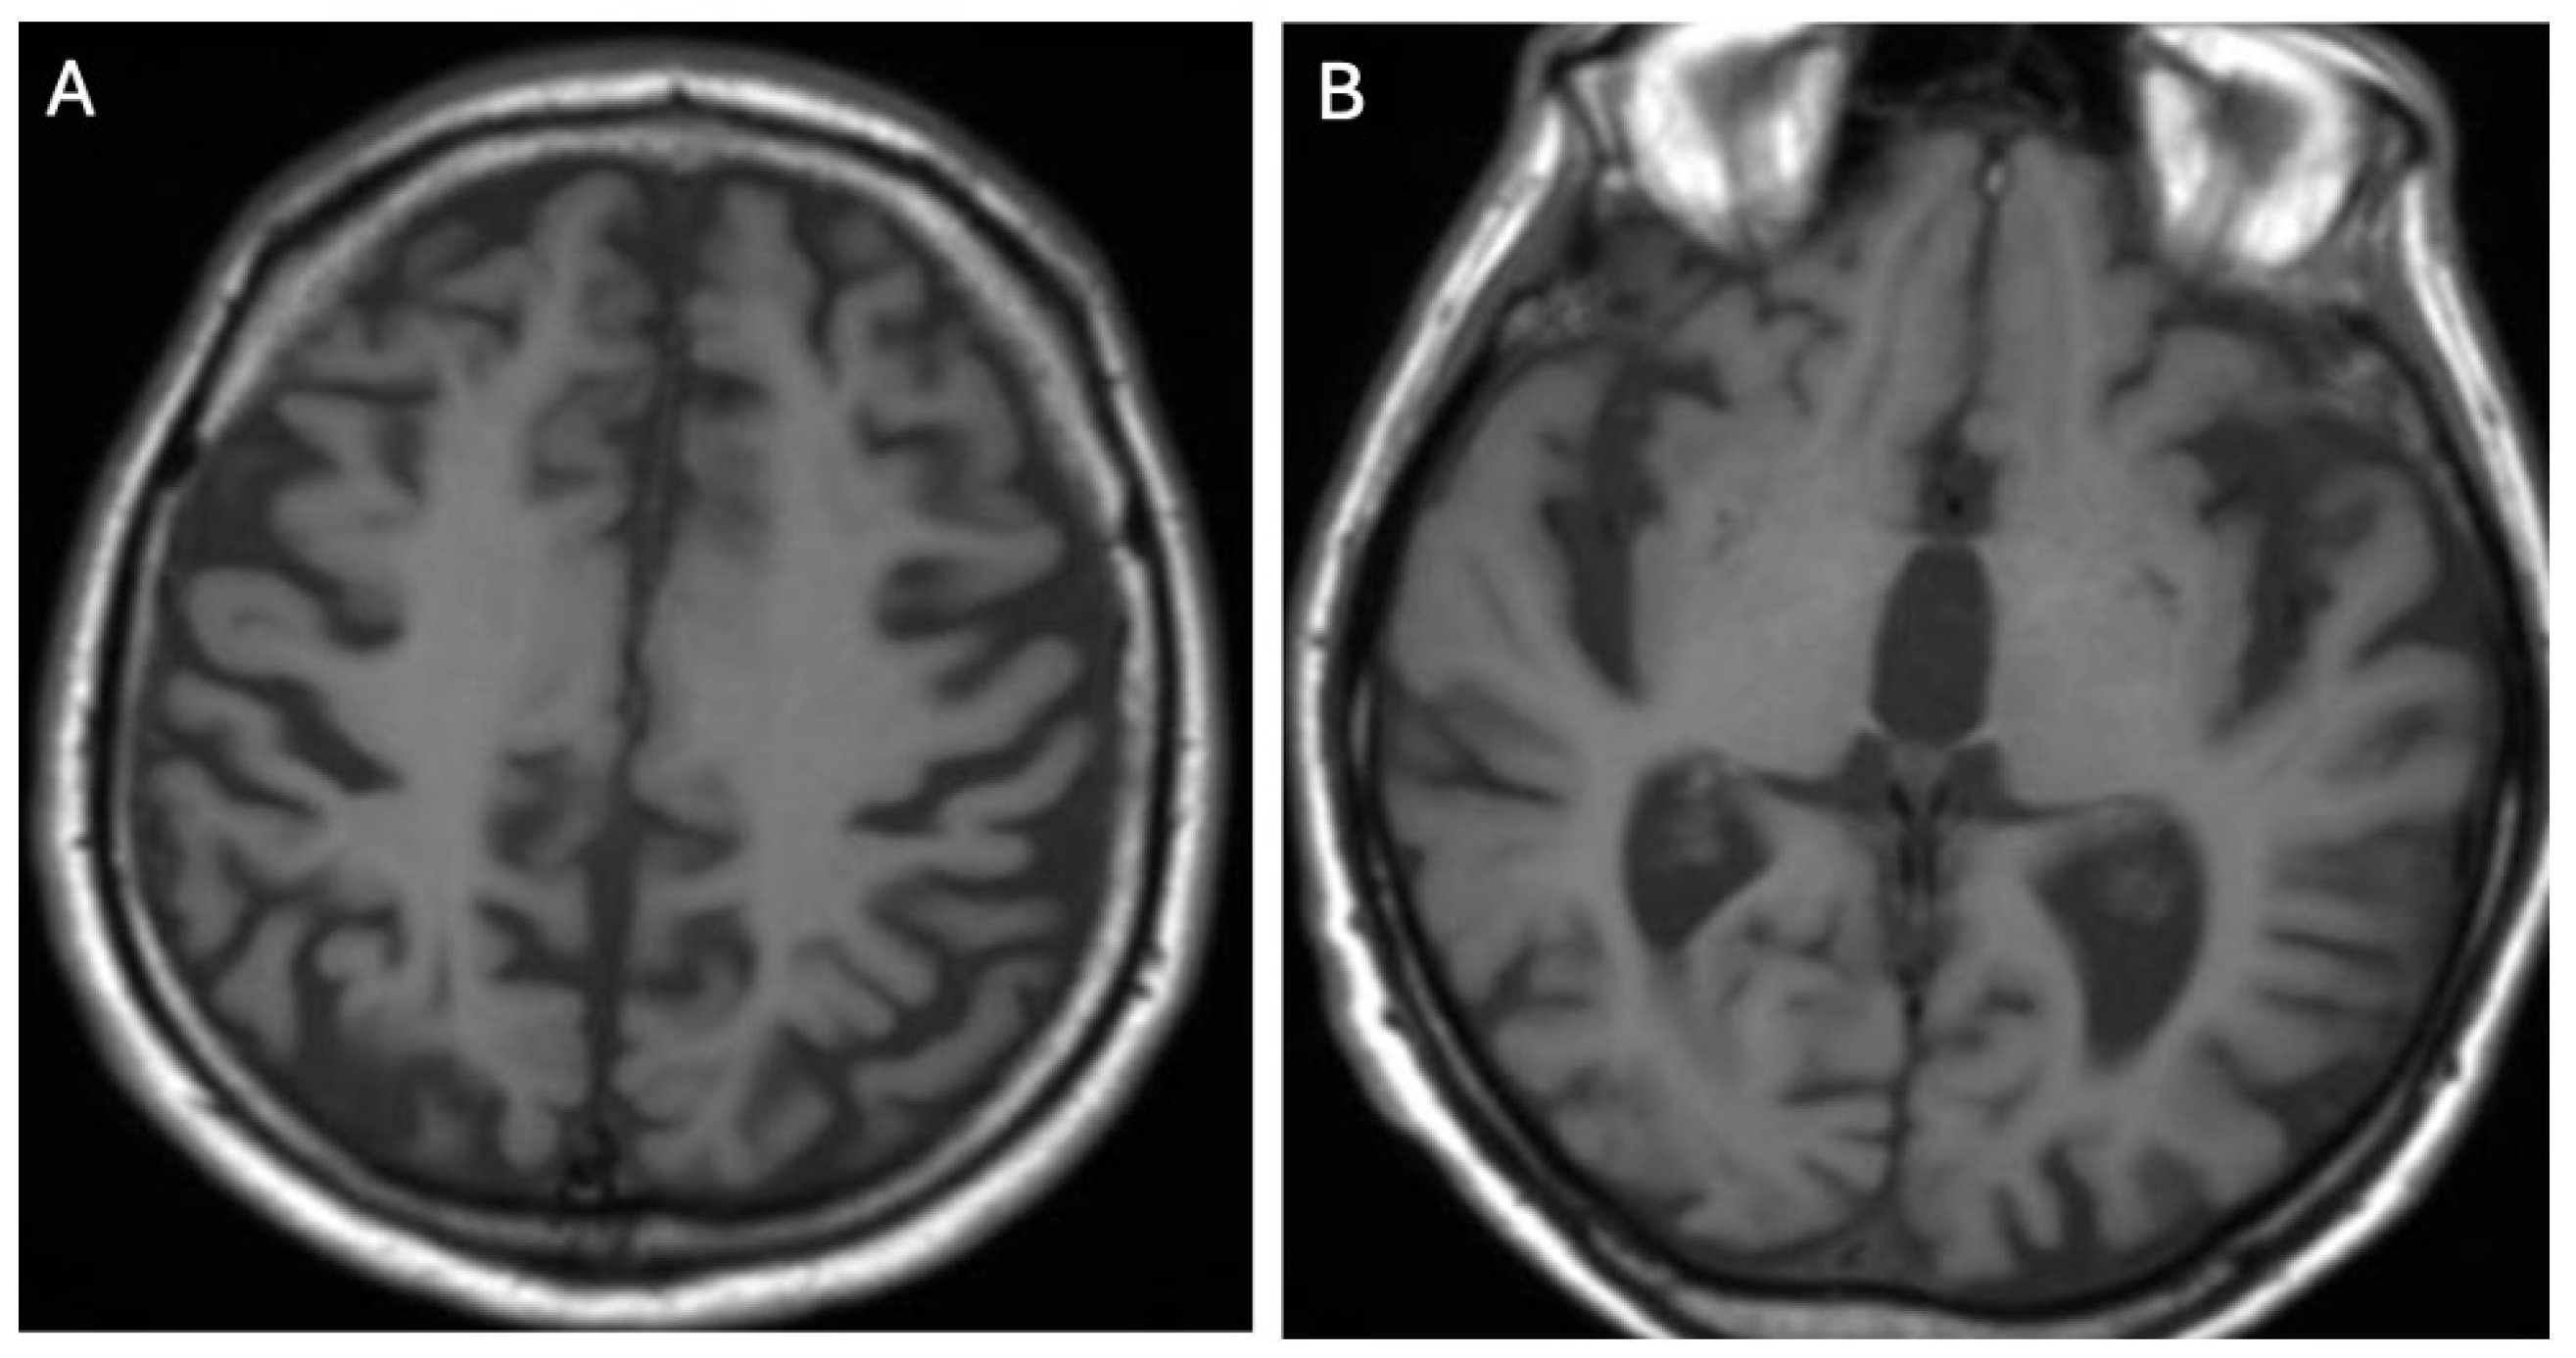

Brain MRI appears to be the most valuable neuroradiological examination for diagnosing WD, differentiating extrapyramidal symptoms, and monitoring anti-copper treatment. Classical brain MRI findings in WD typically include symmetric (rarely asymmetric) hyperintense or mixed-intensity changes in the basal ganglia (globus pallidus, caudate nucleus, thalamus, and/or pons) observed in fluid-attenuated inversion recovery (FLAIR) and T2-weighted sequences [9,12,13,14,15,16,17,18] (Figure 1A,B and Figure 2A,B).

Figure 1.

Hyperintense changes localized in putamen, head of nucleus caudate, and thalamus in T2-weighted sequences (A) and FLAIR (B) (own materials of the neurology department).